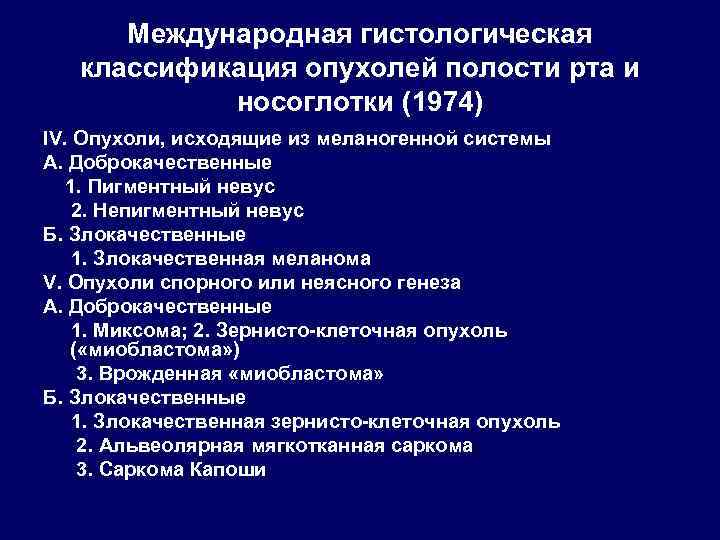

Международная гистологическая классификация опухолей полости рта и носоглотки (1974) IV. Опухоли, исходящие из меланогенной системы А. Доброкачественные 1. Пигментный невус 2. Непигментный невус Б. Злокачественные 1. Злокачественная меланома V. Опухоли спорного или неясного генеза А. Доброкачественные 1. Миксома; 2. Зернисто-клеточная опухоль ( «миобластома» ) 3. Врожденная «миобластома» Б. Злокачественные 1. Злокачественная зернисто-клеточная опухоль 2. Альвеолярная мягкотканная саркома 3. Саркома Капоши

Международная гистологическая классификация опухолей полости рта и носоглотки (1974) IV. Опухоли, исходящие из меланогенной системы А. Доброкачественные 1. Пигментный невус 2. Непигментный невус Б. Злокачественные 1. Злокачественная меланома V. Опухоли спорного или неясного генеза А. Доброкачественные 1. Миксома; 2. Зернисто-клеточная опухоль ( «миобластома» ) 3. Врожденная «миобластома» Б. Злокачественные 1. Злокачественная зернисто-клеточная опухоль 2. Альвеолярная мягкотканная саркома 3. Саркома Капоши